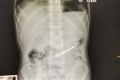

7岁男童误吞5厘米锋利铁钉 医护人员紧急抢救

­“小孩微创手术取出了铁钉,目前病情很平稳!”9月3日,笔者在漳州市医院普外一科了解到,因误吞锋利铁钉的小男孩经医护人员抢救脱险。 ­ ...